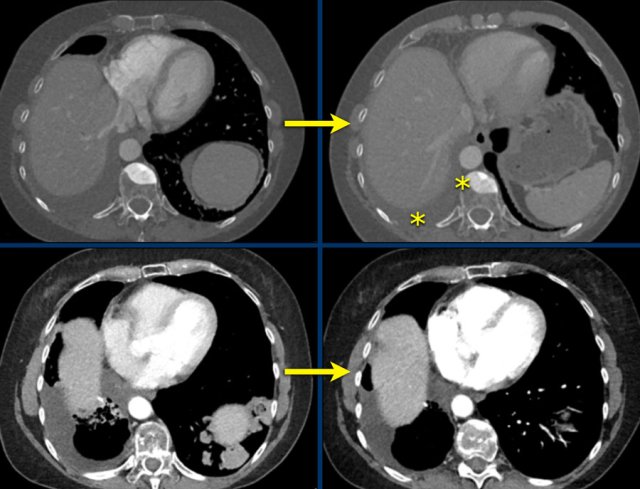

CT images in a 58-year-old male with stadium 4 lung cancer, contralateral pulmonary, lymph node and osseous metastases, and previous treatment with lobectomy of the right lower lobe and chemoradiotherapy.

CT image on the right at response evaluation during treatment with immunotherapy shows complete disappearance of pulmonary metastases.

Does this mean CR?

Continue to the next images.

Although the lungmetastases have disappeared, other images showed unchanged sclerotic bone lesions and pleural effusion.

This makes it impossible to assign complete response, unless these lesions are proven not to be viable or malignant by FDG-PET or cytology.